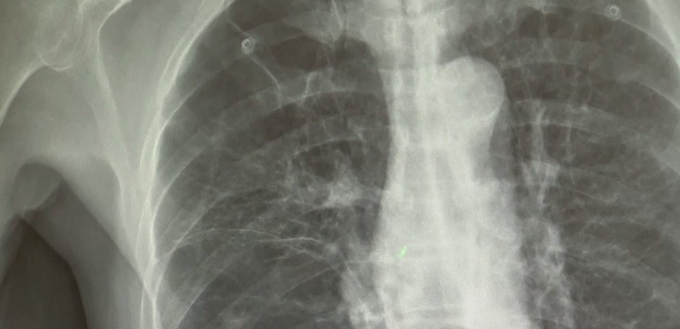

연구진은 2016∼2020년 삼성서울병원과 서울아산병원에서 비소세포폐암을 진단받은 3천명과 폐에 이상이 없는 대조군 3천명을 선정해 위험 요인을 정밀 분석했다. 양 집단은 모두 흡연 경험이 없는 비흡연자였다.

비흡연 환자 중에서 폐결핵 등 폐 관련 질환 병력이 있는 경우 폐암 발병 위험이 대조군보다 2.91배 높았다.

특히 만성폐쇄성폐질환(COPD) 환자의 경우 폐암에 걸릴 위험이 7.26배까지 올라갔다. 연구진은 이러한 위험이 폐에서 계속되는 만성적 염증 반응 때문일 것으로 추정했다.